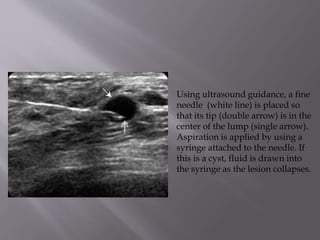

Using ultrasound guidance, a fine

needle (white line) is placed so

that its tip (double arrow) is in the

center of the lump (single arrow).

Aspiration is applied by using a

syringe attached to the needle. If

this is a cyst, fluid is drawn into

the syringe as the lesion collapses.

Using ultrasound guidance,a fine needle (white line) is placed so that its tip (double arrow) is in the center of the lump (single arrow). Aspiration is applied by using a syringe attached to the needle. If this is a cyst, fluid is drawn into the syringe as the lesion collapses.